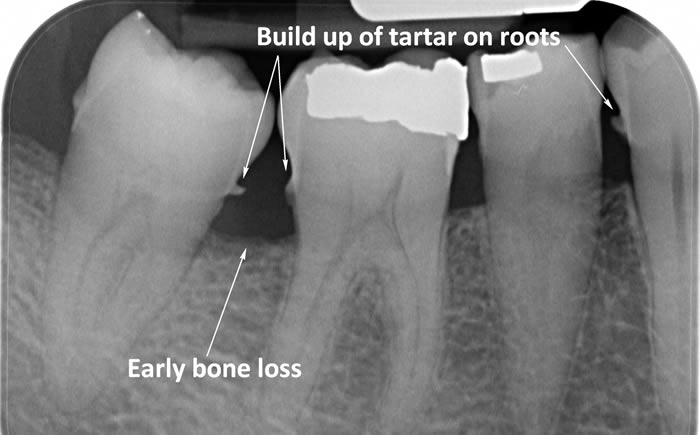

Periodontitis is a more advanced stage of gum disease where there has been damage to the bone which supports the teeth. If left untreated periodontitis leads to more and more bone loss until the teeth start to become loose and eventually fall out by themselves or need to be extracted by a Dentist.

The main cause of gum disease is plaque. Plaque consists of millions of bacteria which live on and around the teeth and gums. These bacteria produce toxins which damage the gums. To begin with the gums start to peel away from the teeth and “pockets” form. As the bacteria penetrate deeper into these “pockets” they then start to cause damage to the bone which holds the teeth in. As more bone loss occurs the teeth start to become increasingly looser until they eventually start to fall out one by one.

The diagrams below show the different stages of gum disease

In addition to helping patients improve their oral hygiene our Hygienist’s will also carry out thorough scaling and polishing to remove any build-up of calculus (tartar) which has formed on the teeth above the gum level.

Calculus (tartar) is the hard deposit which forms on the teeth in areas where plaque is left undisturbed. Calculus is too hard to brush off with a toothbrush and needs to be removed by the Dental Hygienist with special scaling instruments.